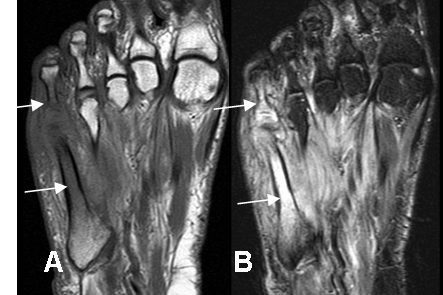

Fig 64. Pie diabético. Osteomielitis.

A: RM axial en T1 y B: RM axial en STIR. Osteomielitis del metatarsiano y la falange proximal del 5º dedo, los cuales son hipointensos en T1 e hiperintensos en STIR (Flechas delgadas). Importantes cambios inflamatorios en los tejidos blandos del mediopié, sin colecciones.